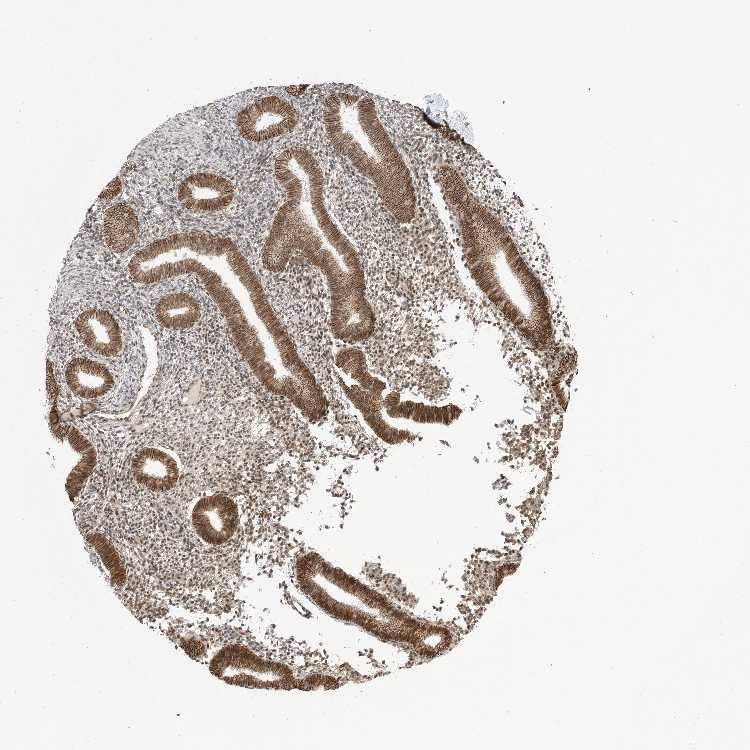

ENDOMETRIUM 1 - Antibody stainingi

Antibody staining in the annotated cell types in the current human tissue is reported as not detected, low, medium, or high, based on conventional immunohistochemistry profiling in selected tissues. This score is based on the combination of the staining intensity and fraction of stained cells.

Each image is clickable and will lead to virtual microscopy that enables deeper exploration of all samples and also displays staining intensity scores, fraction scores and subcellular localization as well as patient and tissue information for each sample.

Antibody HPA034797Antibody HPA034798

Cells in endometrial stroma Not detectedNot detected

Glandular cells LowLow

ENDOMETRIUM 2 - Antibody stainingi

Cells in endometrial stroma LowMedium

Glandular cells LowMedium